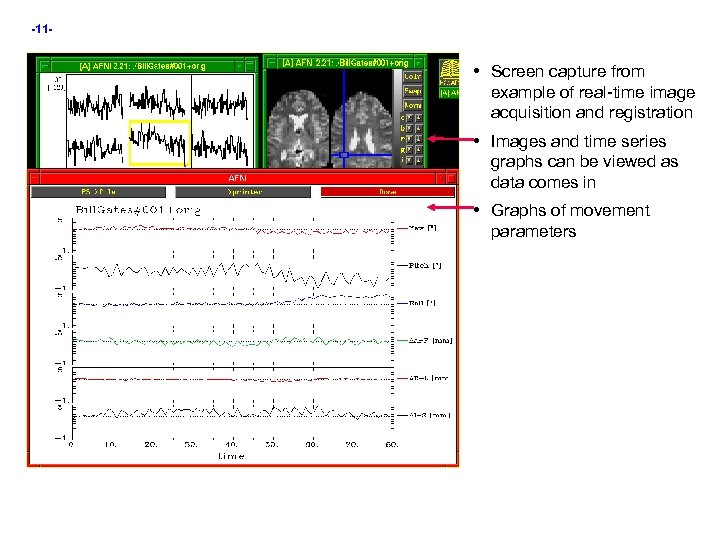

-11 - • Screen capture from example of real-time image acquisition and registration • Images and time series graphs can be viewed as data comes in • Graphs of movement parameters